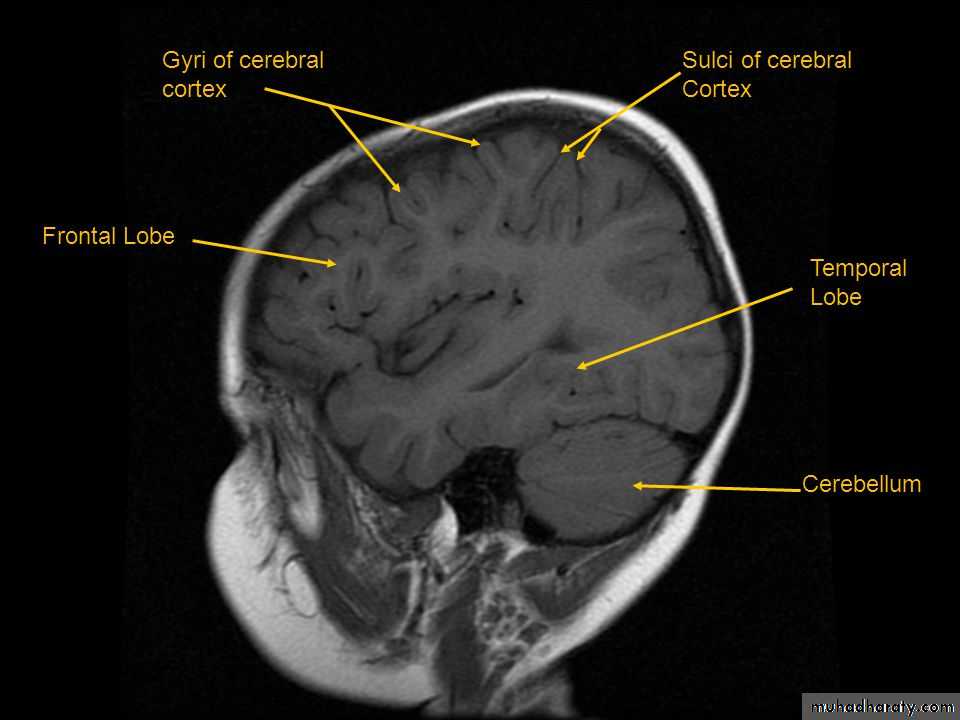

• External features• SurfaceS :

• 1. Superolateral surface• 2. Medial surface

• 3. Inferior surface

• Sulci :

• 1. Central sulcus,• 2. Lateral sulcus,

• 3. Parieto-occipital sulcus,

• Superolateral surface

• 2. Medial surface: